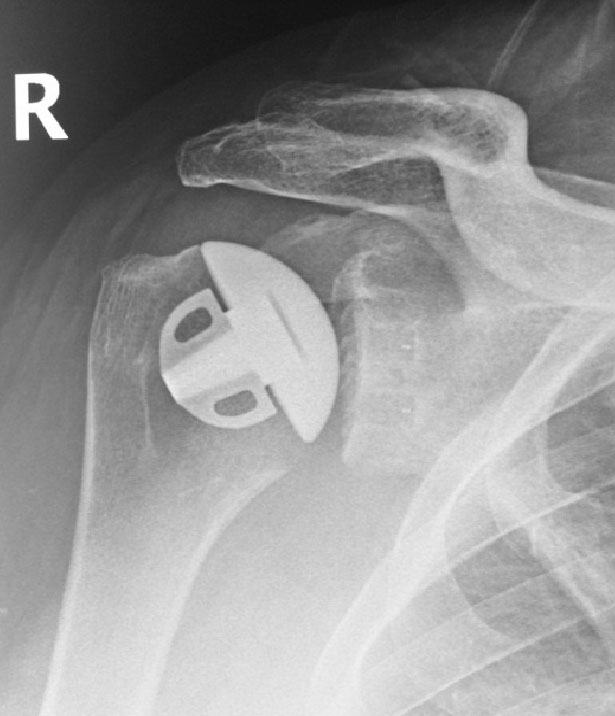

Shoulder after replacement surgery

Move the slider to compare arthritic shoulder with stemless replacement